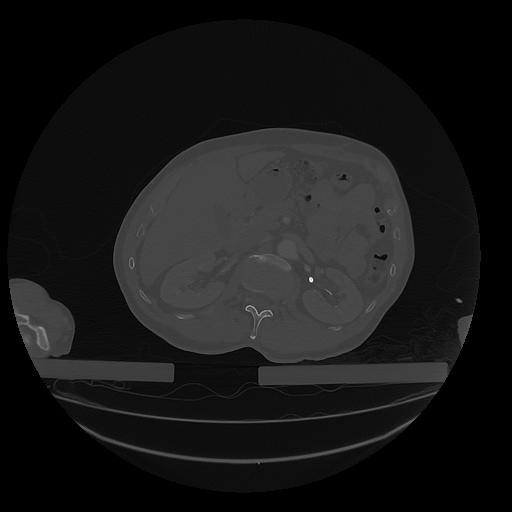

31 PULMON,CE,Vol,1.0,PULMON,,